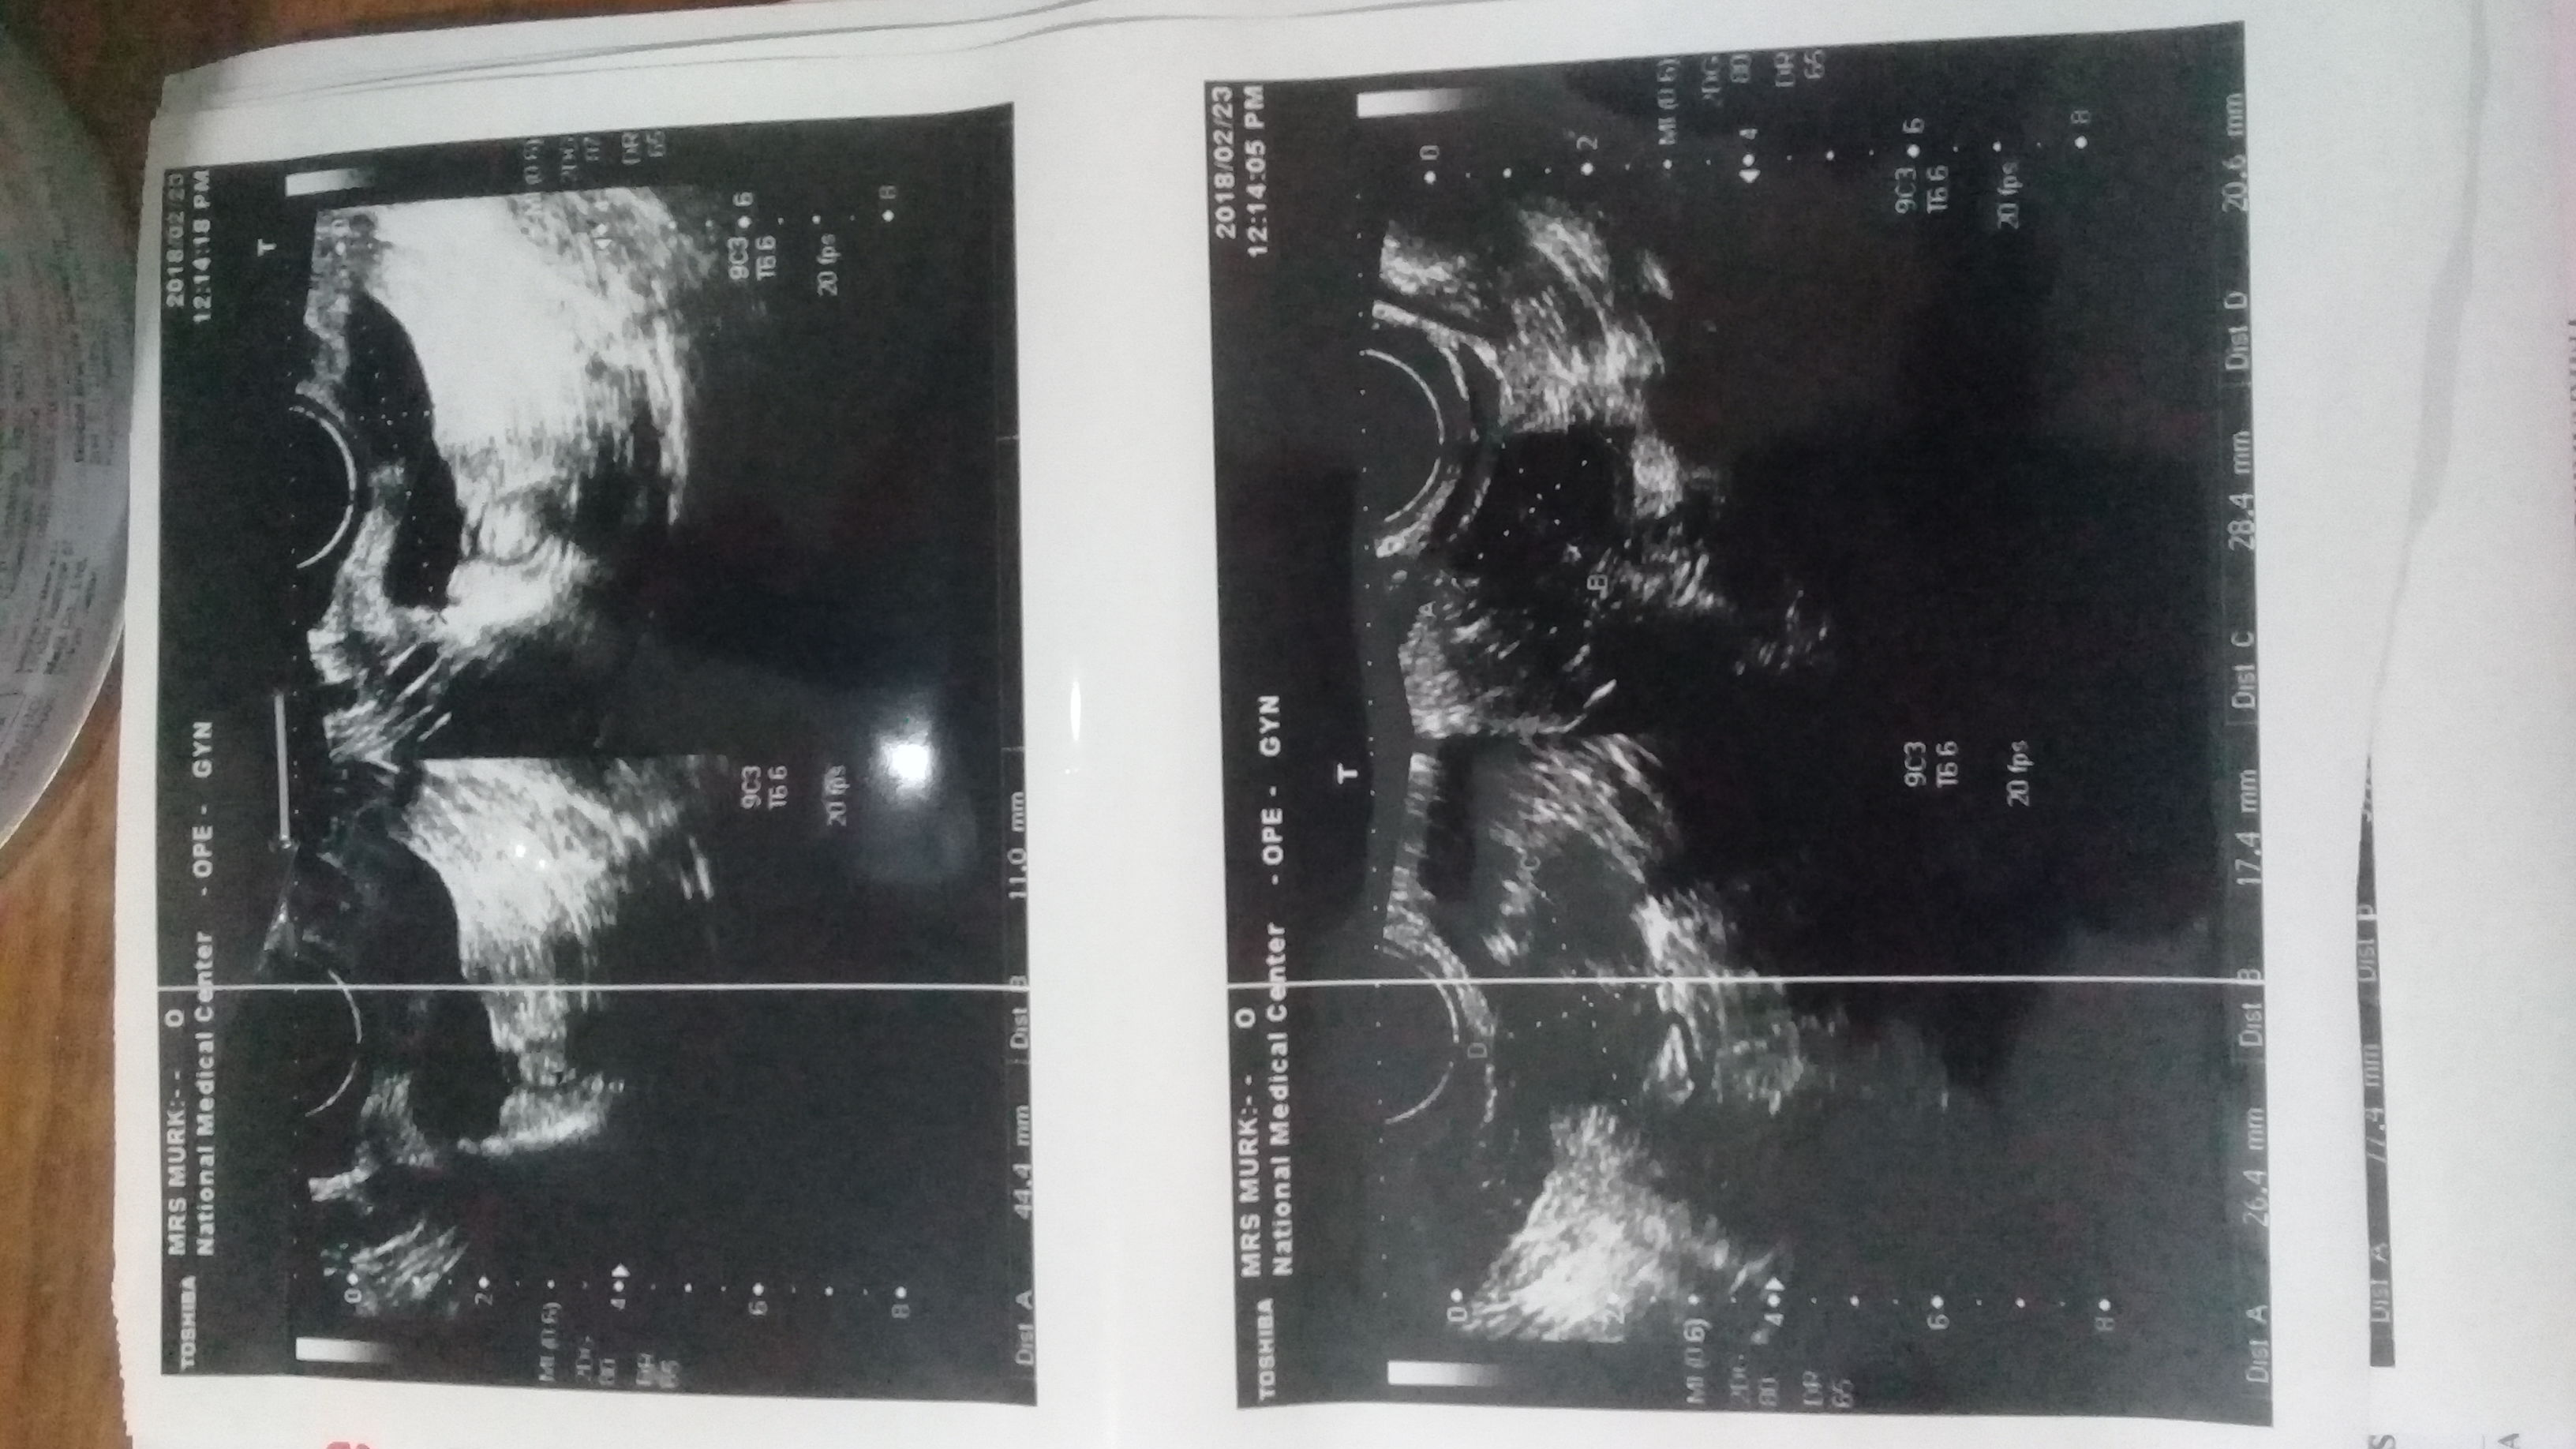

I have completed the coarse of vibramycin and flagyl for 7 days but still having throbbing pain have Ben to gyneacologist she said u have adhesions in pelvic area which makes more often infections again and again although this is first time experiencing such condition and she also suggest u have pco does my scan shows anything like this pls put light on it